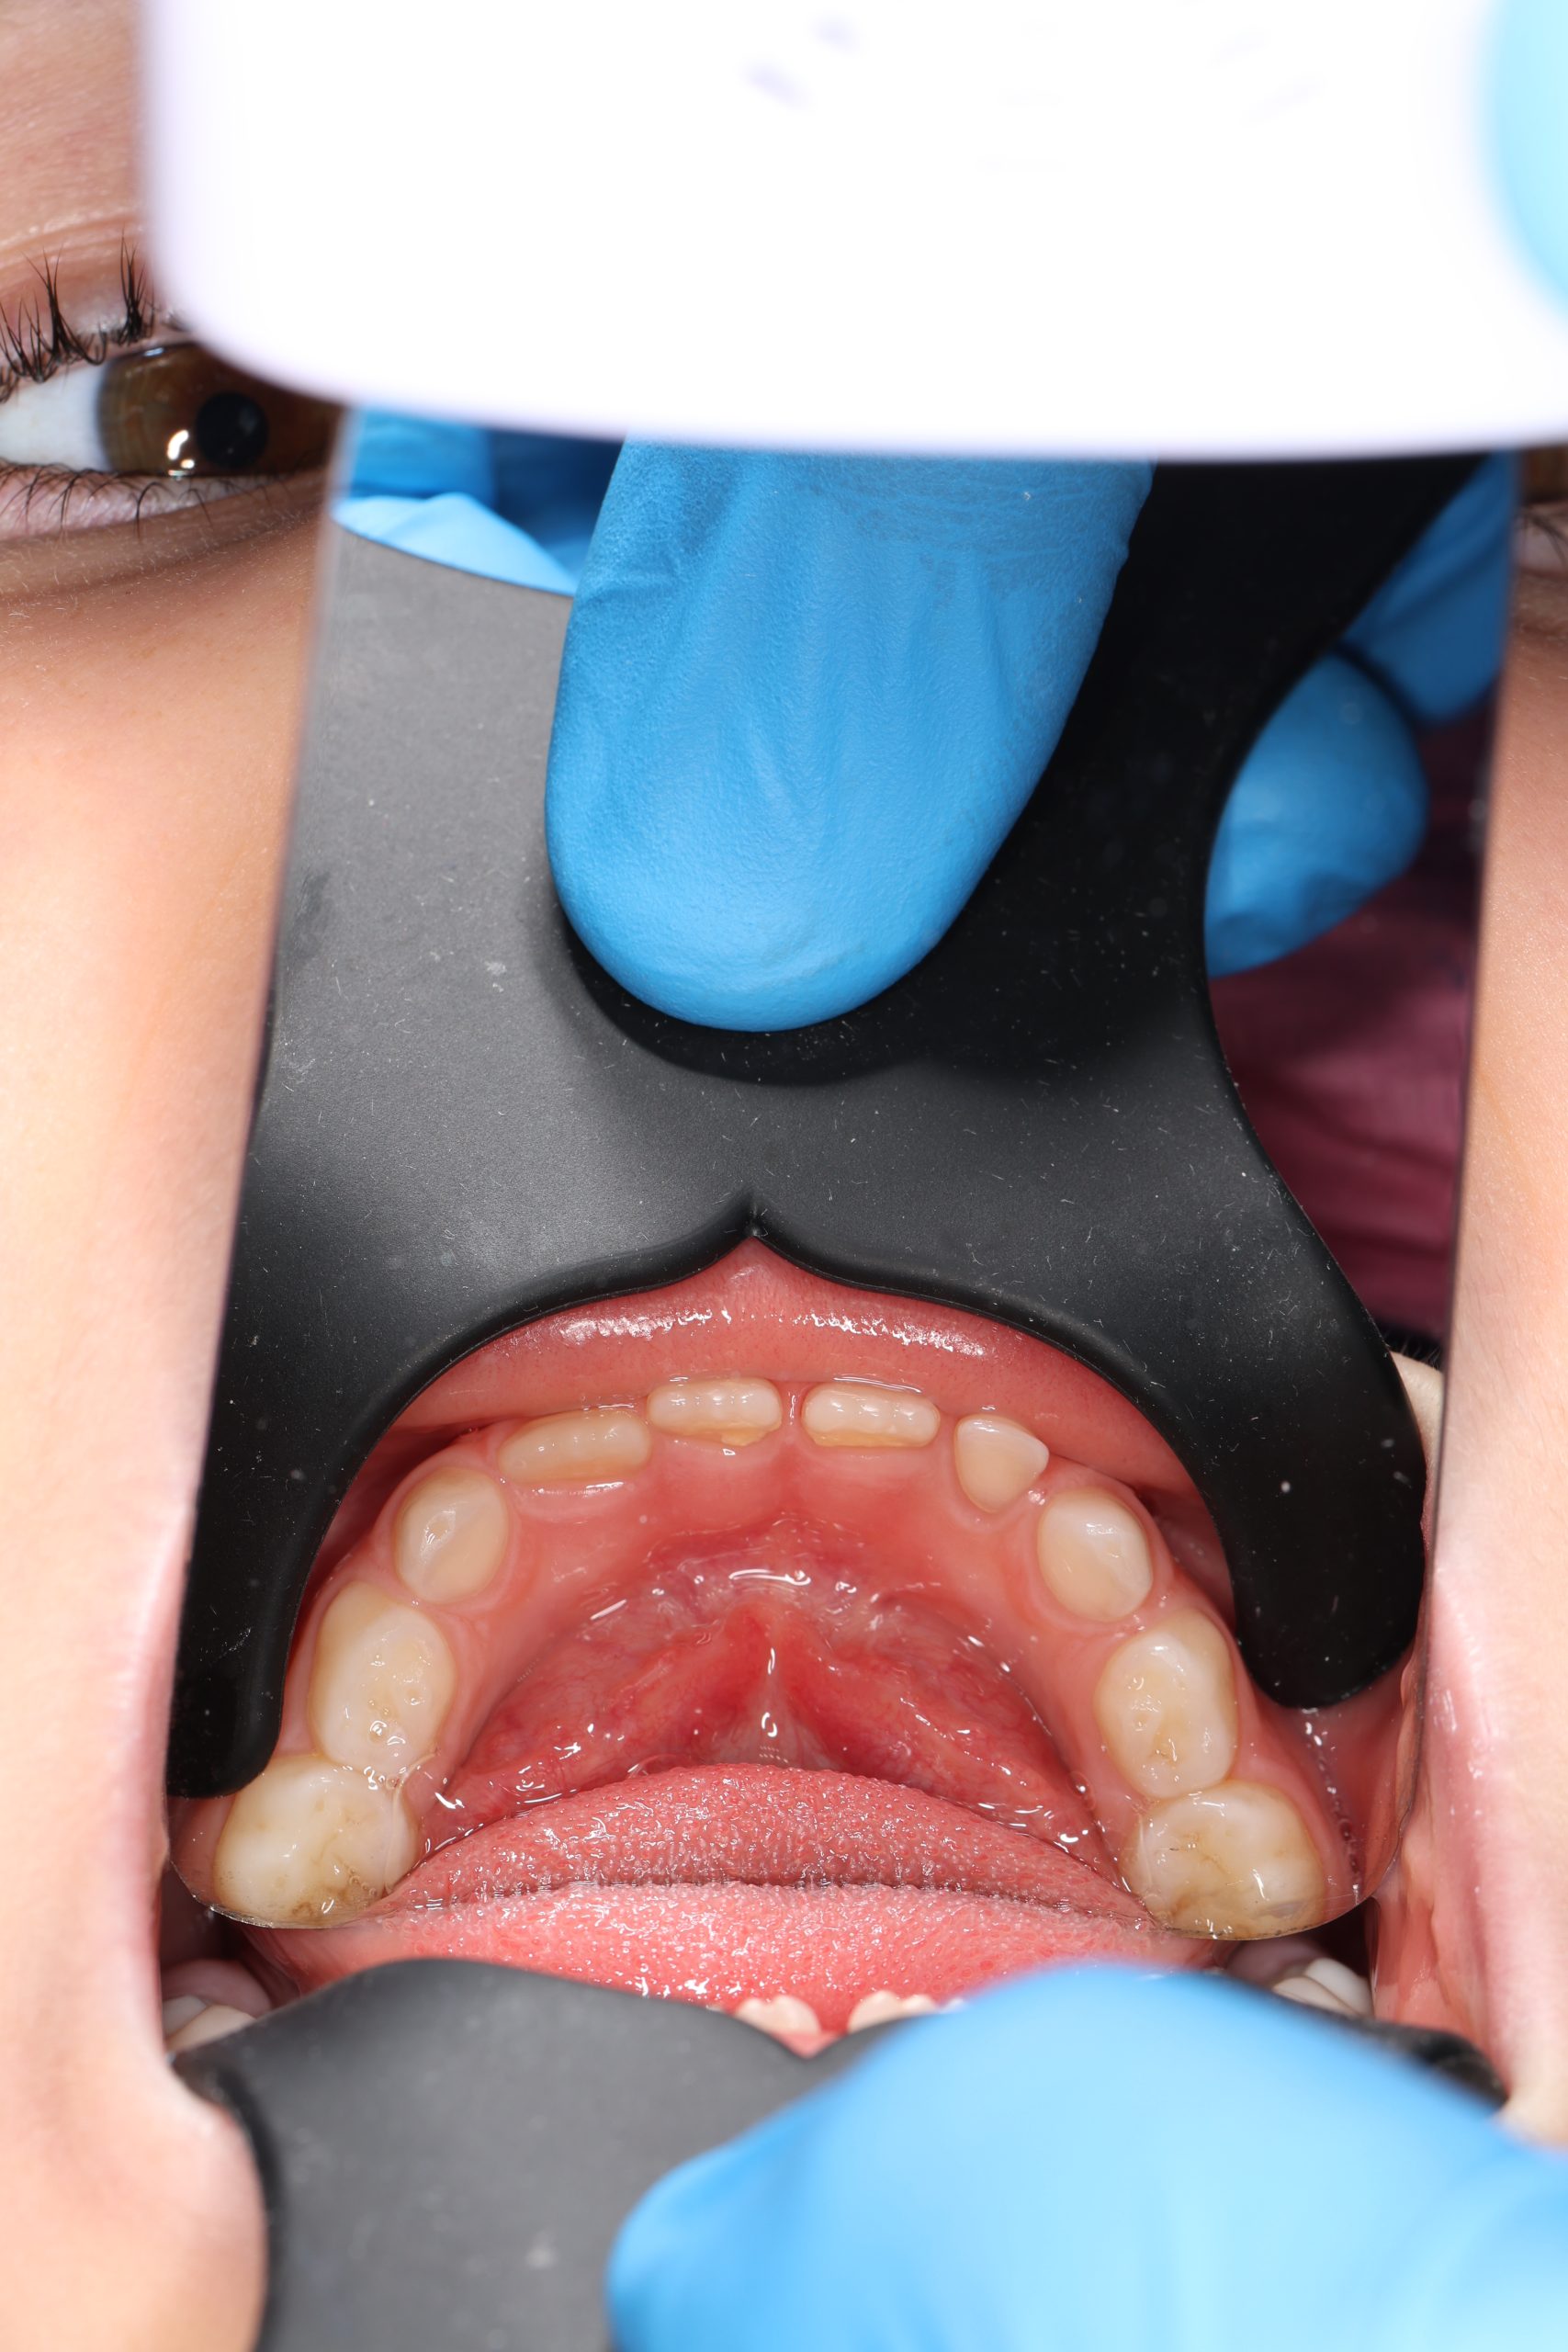

We examine the condition of teeth, gums, and bite. - Plaque Disclosure with Special Indicators

Areas that weren’t cleaned well appear purple. The darker the shade, the older the plaque. This helps both kids and parents understand where brushing needs to improve. - Brushing Training & Home Care Tools Selection

Together with your child, we practice brushing techniques, correct mistakes, and provide personalized recommendations. We advise whether to use manual or electric brushes, floss, interdental brushes, or remineralizing gels. - Plaque Removal with AIRFLOW Prophylaxis Master (EMS, Switzerland)